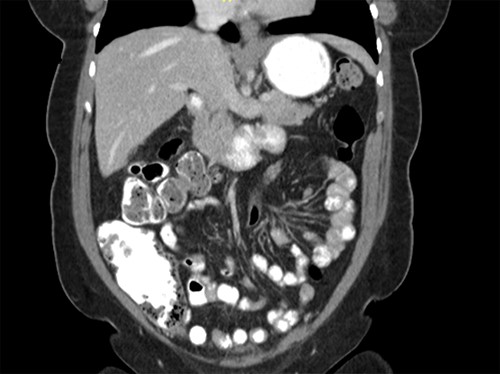

CT scan of the abdomen showing the absence of the gallbladder within the gallbladder fossa. This image also depicts the absence of malrotation of the gut or horseshoe kidney.

agenesis as seen in Fig. 1. The port sites were sutured closed, and no post-operative complications were noted. It was concluded that the adhesions were causing the patient’s chronic abdominal pain which resolved. A computed tomography (CT) scan of the abdomen seen in Figs 2 and 3 confirmed the absence of a gallbladder with no associated pathology depicted.